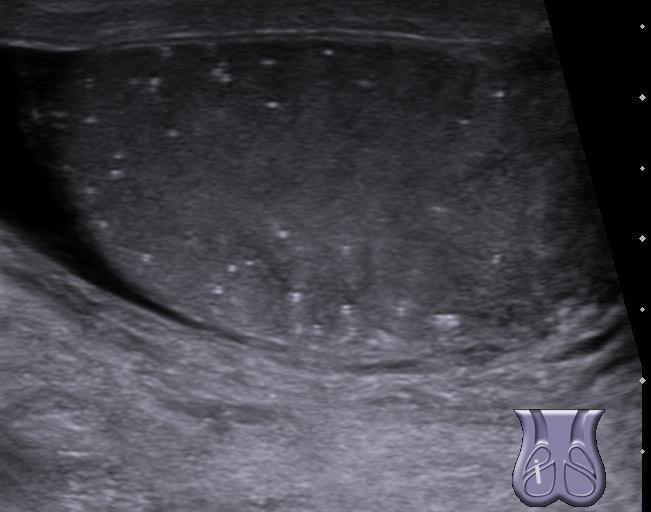

睾丸微石症

睾丸微石症是一种超声诊断的睾丸异常情况。可见于1.5%至5%的正常男性,而在生育力低下的个体中可高达20%。它是无症状的非进行性疾病。病因不明,但这种情况在一小部分人群里与睾丸癌有关,如隐睾,腮腺炎,不育和上皮内生殖细胞瘤样病变。典型的睾丸微石症被定义为在一个或两个睾丸里每视图中有五个或以上的回声灶,而有限的睾丸微石症被定义为仅有一个或以上回声灶,还达不到典型睾丸微石症的标准。在80%的情况下,两个睾丸都受到影响。

睾丸微石症是一种罕见的情况 – 睾丸超声检查时被诊断 --- 睾丸内一簇钙化。多项研究曾表明睾丸微石症和睾丸癌之间有关系。不过,目前还不清楚睾丸微石症是否是睾丸癌的独立危险因素。